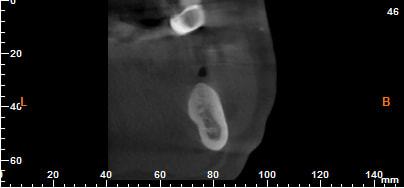

coupe demandé sur le suivi du canal dentaire

--

12X8.5cm

0.2mm